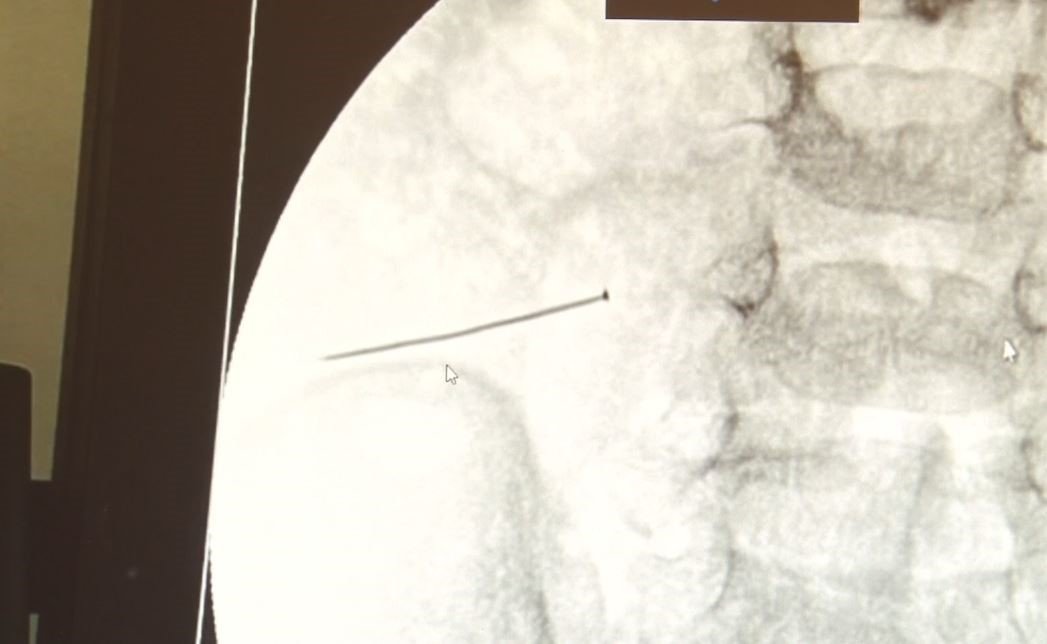

Öte yandan, yaklaşık 3 santimlik toplu iğne filme yansıyan görüntüsüyle gözler önüne serildi.

İstanbul’da 2 yaşındaki çocuk iddiaya göre toplu iğne yuttu sonrasında adeta karın ağrısıyla yerinde duramaz hale geldi. Babaanne, küçük çocuğun şikayetleri üzerine Şehit Prof. Dr. İlhan Varank Sancaktepe Eğitim ve Araştırma Hastanesi’ne götürdü. Burada yapılan tetkiklerde 2 yaşındaki çocuğun ince bağırsağında yaklaşık 3 santimlik toplu iğne olduğu ve bağırsağı deldiği belirlendi. Görüntülemeler sonrası 30 Ekim akşamı Çocuk Cerrahisi Kliniği Eğitim ve İdari Sorumlusu Doç. Dr. Sefa Sağ ve ekibi hemen ameliyata girdi. Başarılı operasyonla iğne olduğu noktadan alınırken aile de rahat bir nefes aldı. Doç. Dr. Sağ ise taburcu edilen hastasının durumuna ilişkin bilgi verirken yabancı cisim yutmalarına karşı ailelere önemli uyarılarda bulundu.

Çocuklarda yabancı cisim yutulmasına yönelik konuşan ve hastasına ilişkin bilgi veren Doç. Dr. Sefa Sağ, “Soluk borusuna kaçması durumunda çocuğun Allah göstermesin ölümüyle veya ömür boyunca yatağa bağımlı kalmasıyla neticelenebilecek sonuçlar doğurabiliyor. Yutulması durumunda da gastrointestinal sistemin herhangi bir yerine takılmadığı müddetçe ekseriyâ yabancı cisimlerin dışarıya çıkmasını bekliyoruz. Yabancı cisim yutulmasını 2 grupta inceleyebiliriz. Sıvı ve katı cisimler olarak sıvı; evde kullanılan kimyasal temizlik malzemelerinin yutulması çok ciddi problemler oluşturabilmekte. Ağızda, yemek borusunda ve midede yanıklar meydana getirebilmekte. Uzun dönemde çocukların hayat kalitesini oldukça etkileyen sonuçlar doğurabilmekte. Katı cisimlerden de ekseriyâ kendiliğinden çıkmasını bekleriz ancak böyle delici, kesici aletlerin yutulmasında ise herhangi bir bağırsağın veya gastrointestinal sistemin bir parçasında delinmeler meydana getirebiliyor. Bu çocuğumuzda da aynen böyle bir hadise meydana gelmişti. Sanırım 1 gün önce ailenin yuttuğunu tahmin ettiği bir yabancı cisim; toplu iğne. Ertesi gün bağırsakta delinmeyle sonuçlanmış ve çocukta da ciddi semptomlar meydana getirmişti. Bu şekilde hasta bize başvurdu. Tetkikler sonucunda yabancı cismi tespit ettik, semptomları ve bulgularına göre de çocuğu ameliyata aldık. Yaklaşık 3 santim boyunda bir toplu iğnenin ince bağırsağı deldiğini, ince bağırsaktaki içeriğin de karın içerisine dolduğunu gördük. Ameliyatı başarılı bir şekilde tamamladık, yaklaşık 1 saat süren bir ameliyattı” dedi.